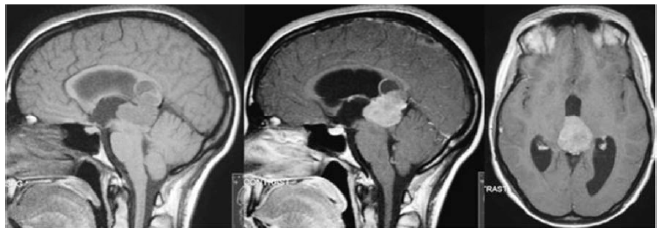

Um paciente de 28 anos de idade, previamente hígido, queixa-se de cefaleia de intensidade progressiva há duas semanas, associada a vômitos e à turvação visual. Ao exame físico, observa-se sonolência e desorientação, bem como papiledema à fundoscopia, paresia do olhar conjugado para cima e nistagmo em convergência. Traz consigo a ressonância magnética de crânio mostrada a seguir, que foi realizada após pedido de médico no posto de saúde.

enunciado 323575-1

O diagnóstico mais provável para esse caso hipotético é o de